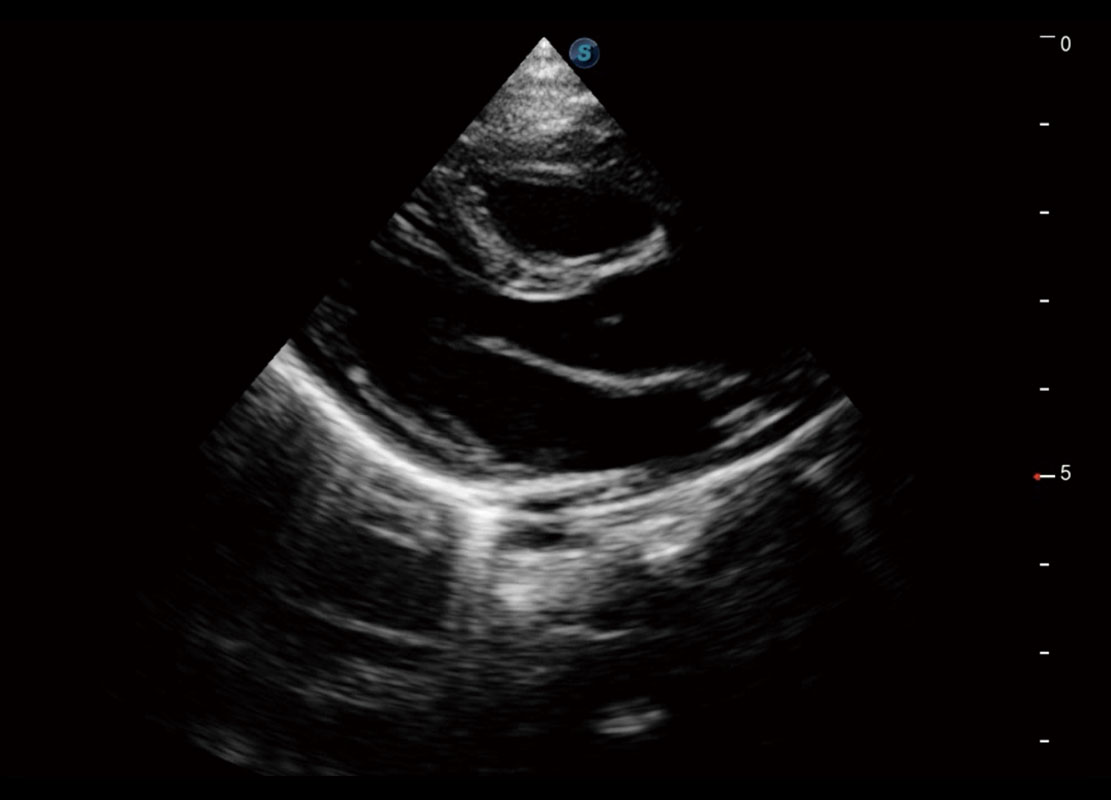

四腔切面